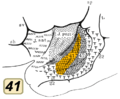

BA42 BA41. Inside lateral sulcus.

BA41. Inside lateral sulcus. BA42. Inside lateral sulcus.